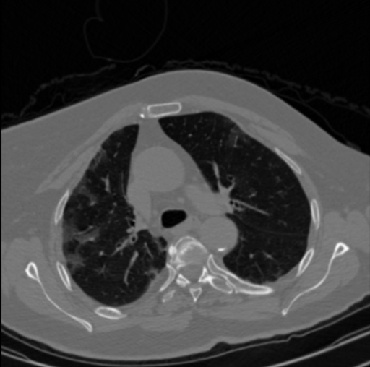

Early and reliable COVID-19 diagnosis based on chest 3-D CT scans can assist medical specialists in vital circumstances. Deep learning methodologies constitute a main approach for chest CT scan analysis and disease prediction. However, large annotated databases are necessary for developing deep learning models that are able to provide COVID-19 diagnosis across various medical environments in different countries. Due to privacy issues, publicly available COVID-19 CT datasets are highly difficult to obtain, which hinders the research and development of AI-enabled diagnosis methods of COVID-19 based on CT scans. In this paper we present the COV19-CT-DB database which is annotated for COVID-19, consisting of about 5,000 3-D CT scans, We have split the database in training, validation and test datasets. The former two datasets can be used for training and validation of machine learning models, while the latter will be used for evaluation of the developed models. We also present a deep learning approach, based on a CNN-RNN network and report its performance on the COVID19-CT-DB database.